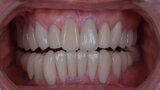

Figure 27 Anterior guidance